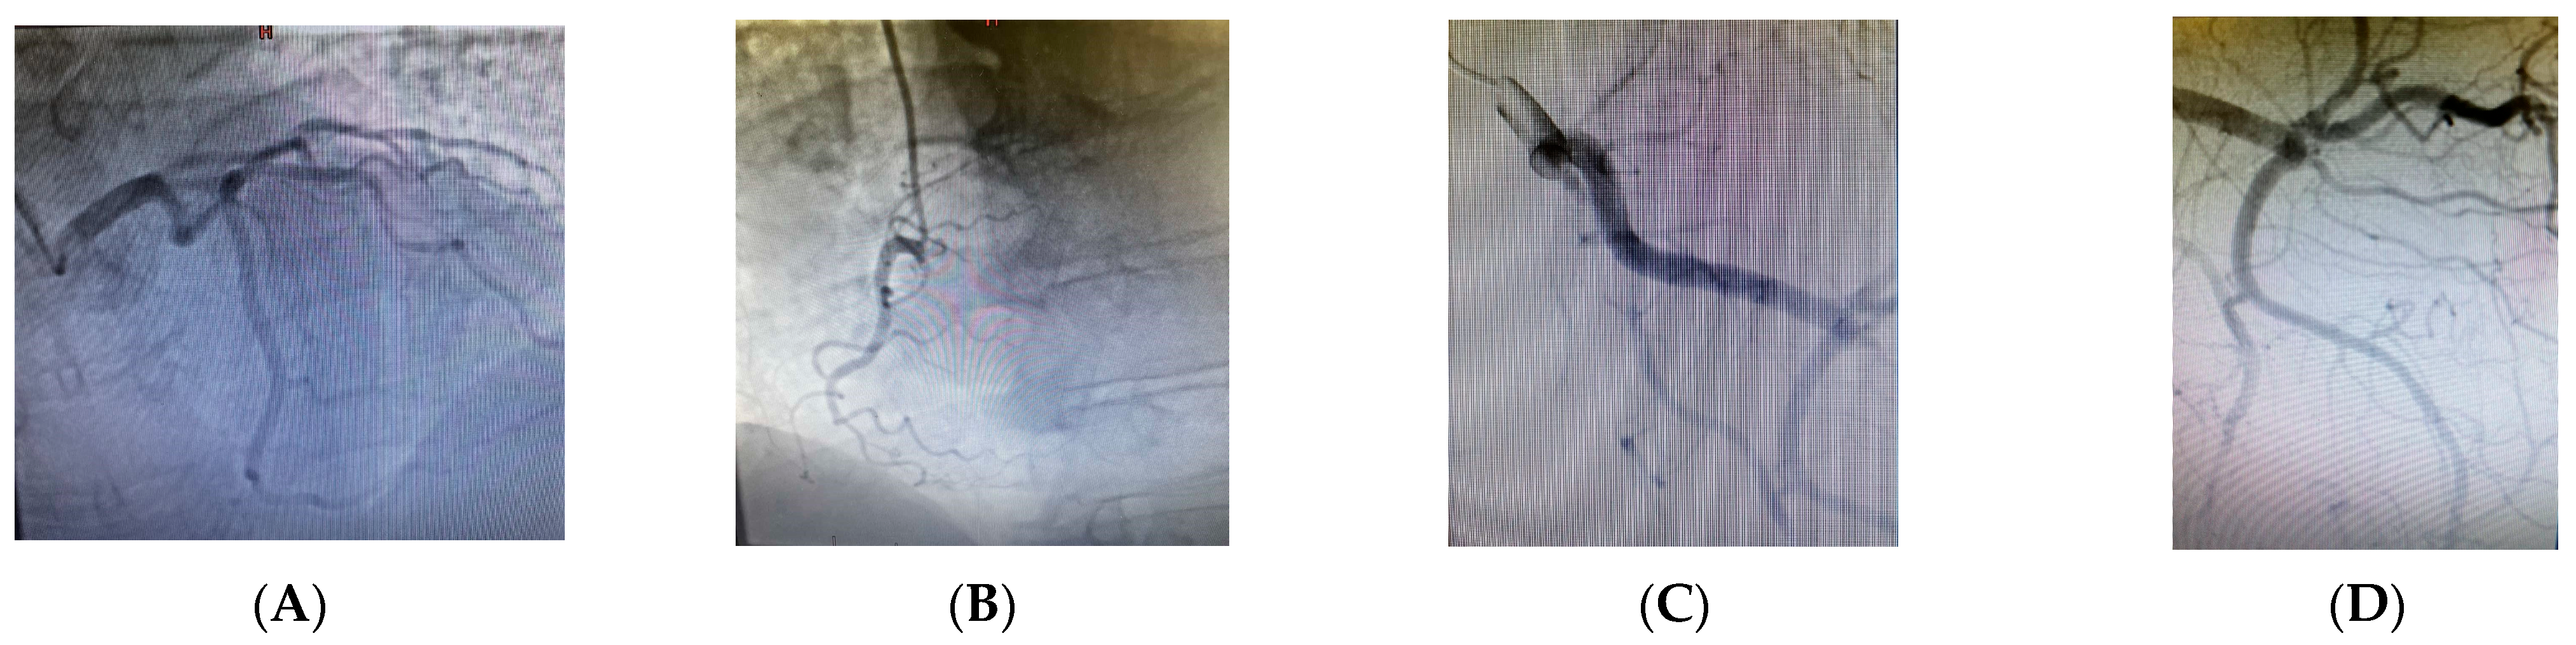

Due to the underlying DVT, the right lower extremity was bandaged with an elastic compression bandage. In response to the ischemia of the left lower extremity, intravenous treatment with pentoxifylline was initiated at a dose of 200 mg diluted in 500 mL of normal saline, administered over 60 min. The decision to initiate pentoxifylline therapy was based on clinical judgment in the context of acute limb ischemia, where immediate improvement in microcirculation was critical. Although not a first-line treatment for acute arterial thrombosis, pentoxifylline has demonstrated efficacy in peripheral vascular disease through its hemorheological effects, enhancing red blood cell flexibility, reducing blood viscosity, and decreasing platelet aggregation. These mechanisms improve tissue oxygenation and perfusion in ischemic regions, justifying its use as a supportive measure in this urgent clinical scenario [24]. Given the persistence of ischemic signs in the left lower extremity and the high risk of surgical intervention, invasive angiographic evaluation was performed through access via the right radial artery. This approach was undertaken after initial stabilization and prioritization of anticoagulation therapy. Angiographic imaging of the coronary arteries showed no evidence of atherosclerotic plaques (Figure 7A–D). The decision to perform coronary angiography was driven by the need to ensure cardiovascular safety before potential surgical revascularization [25], particularly in light of the possibility that percutaneous peripheral artery revascularization might fail. In the context of acute limb ischemia and multiple cardiovascular risk factors, it was essential to exclude significant coronary artery disease before undertaking high-risk vascular surgery [26,27]. Furthermore, the decision to perform coronary angiography was justified by evidence from a study demonstrating that 55% of patients with symptomatic lower limb arterial disease also had significant, yet clinically silent, coronary artery disease, highlighting the importance of proactive cardiovascular risk assessment in this population [28].

Figure 7. (AD) Angiographic imaging of the coronary arteries showing no evidence of atherosclerotic plaques.